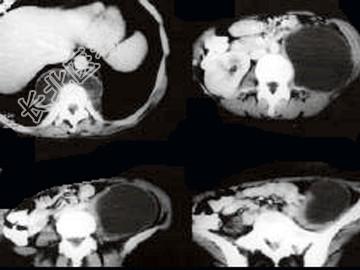

- 单项选择题女,34岁, 咳嗽,腰背疼痛二年, CT检查如图,最可能的诊断是 ( )

A、结核性脓肿

B、囊肿

C、淋巴管瘤

D、卵巢囊肿

E、卵巢囊腺瘤